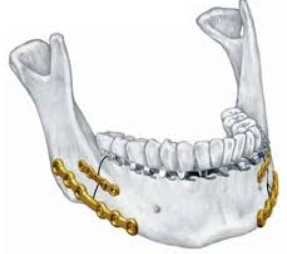

Fractured jaws may require open reduction surgery, jaw wiring for immobilization, and dental crowns and braces to restore a normal bite. Lacerations may need suturing.